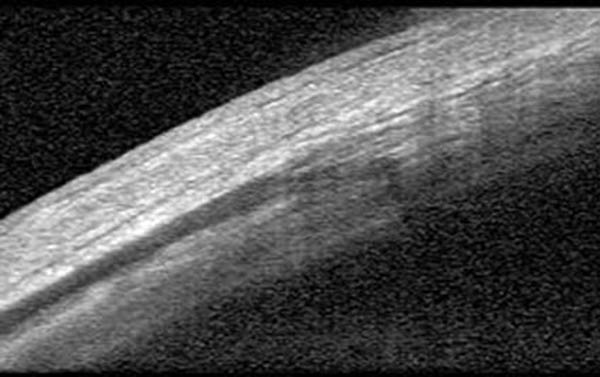

Figura 5:

Magnificación de la imagen de la figura 04.

Figura 4:

Observación de la esclera en pacientes con hipotonía persistente aún con parche escleral. La esclera presenta desorganización de las lamelas de fibras de colágeno y áreas hiporreflectivas.